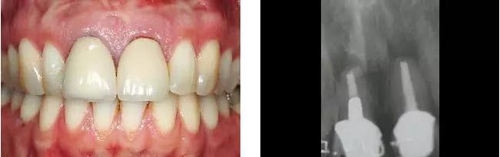

圖1、外形較大的雙側(cè)上中切牙唇側(cè)有瘺管,預(yù)后不佳,患者高笑線、薄齦生物型。

圖2、放射線片顯示雙側(cè)中切牙根尖均有感染病變。